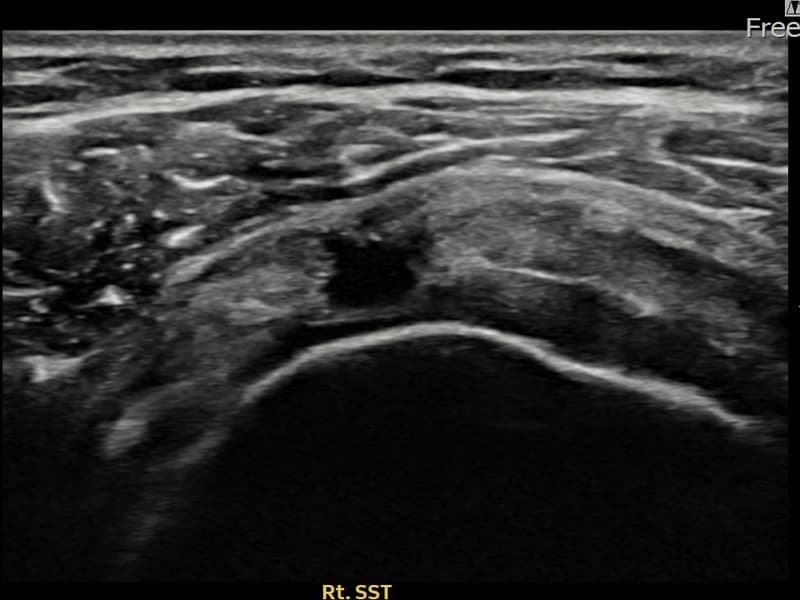

Before

시술 전 초음파 측정 결과 파열 크기는 12mm × 7mm (힘줄 두께의 약 55% 결손)로 확인되었습니다. 시술 전 초음파에서 우측 극상근건의 광범위한 에코 단절과 힘줄 내 복합 소견이 확인되었습니다. 시술 후 초음파에서 파열 부위에 재생 조직이 형성되며 힘줄 연속성이 회복된 것이 관찰되었습니다.

50대 중반 남성 환자분으로, 우측 어깨 통증이 오래되어 파열이 상당히 진행된 상태였습니다. 다방향에서 초음파 평가를 시행한 결과 관절면측 파열이 넓게 퍼진 진행형 소견이 확인되었습니다. 파열 범위가 넓어 일반 보존 치료로는 한계가 있다고 판단하여 초음파 유도 하 축소봉합술을 시행하였습니다. 시술 후 충분한 보조기 착용 기간을 유지하고 단계적 재활을 진행하였으며, 14주 후 추적 초음파에서 파열 부위의 구조적 안정화가 확인되었습니다.